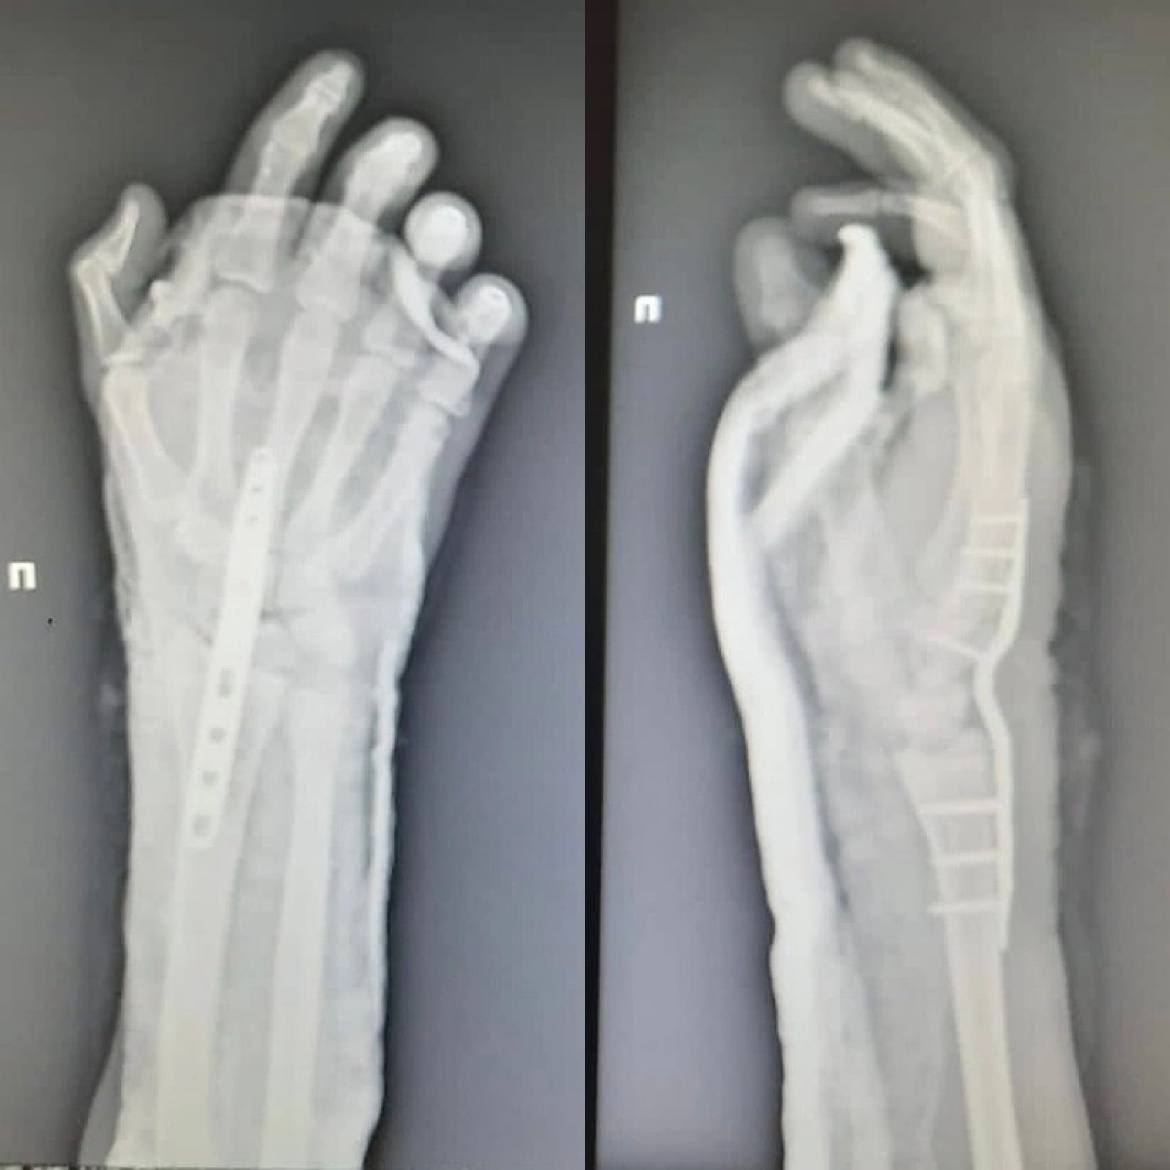

Нижегородские врачи пришили руку подростку

Нижегородские врачи помогли подростку, который отрубил себе кисть руки при колке дров.

Медики провели 16-летнему пациенту операцию по реимплантации конечности. Сейчас его состояние стабильно, кровоснабжение кисти восстановлено. Парню понадобится еще несколько операций, чтобы восстановить функциональность кисти.